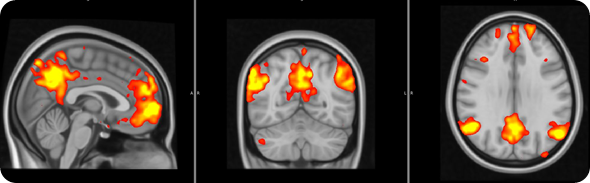

We saw that the healthy subjects showed large brain responses, in many regions, when they were anticipating pain or relief. Some of these changes are likely to be due to the detection of ‘salient’ event. In other words, some of these responses may be non pain-specific and may simply reflect the fact that the subjects were detecting an ‘interesting event’.

However, other responses would seem to be even more interesting, and possibly pain specific: for instance the healthy volunteers activated a region called the ‘periaqueductal gray region’, which we know exerts a modulatory effect on the pain signals coming to the periphery (this is a region that if stimulated electrically can alleviate pain).

The healthy volunteers also showed that a region involved in the processing of ‘reward’/’punishment’, the so called ventral tegmental area (VTA), was activated during pain anticipation, and deactivated during relief anticipation.

FM patients exhibited reduced brain responses in response to visual cues for both pain anticipation as well as relief anticipation.

This reduced responsiveness was very widespread, and included the periaqueductal gray and the VTA.